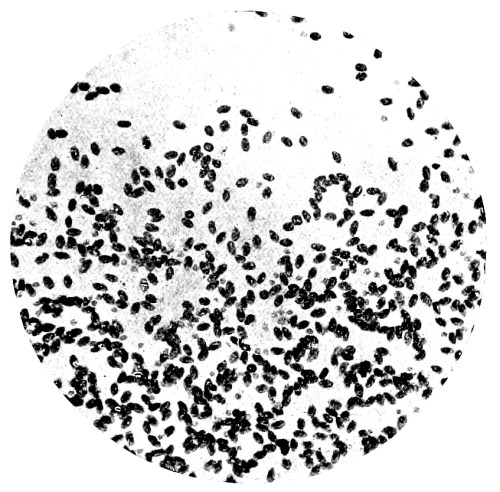

| 21. | Photo-micrograph of Human Spermatozoa | 147 |